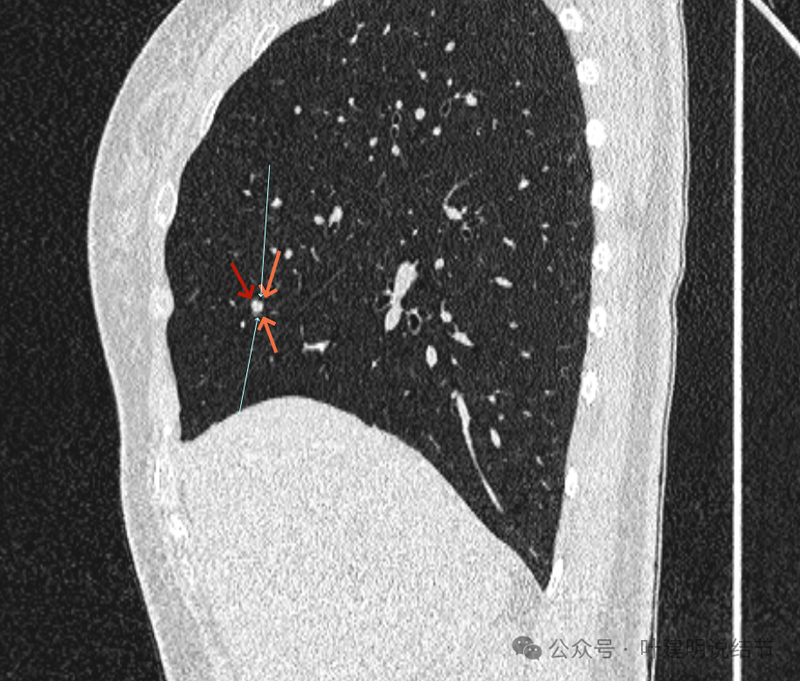

再看矢状位影像:

桔色的是血管,红色的是病灶,两者之间有间隙仍用天蓝色细线标注。

紧挨但仍有缝隙的。

血管贴着病灶,病灶表面略有毛糙之处。

血管有形成轻微血管弯征,两者紧贴。

两支血管夹着病灶,密度不同,有低密度间隙。

病灶与两侧血管关系均密切,明显觉得密度是不一样的,血管的密度略高,结节的略低。